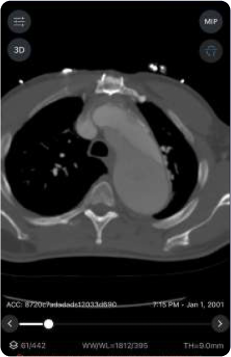

The first study, "Automated PE Clot Detection and RV/LV Ratio Measurement using AI-based Deep Learning Algorithms: A Preliminary Validation Study," evaluated the performance of Viz PE and Viz Right Ventricle/Left Ventricle (RV/LV) algorithms. The study found that, across 100 retrospectively-collected chest CTPA images, Viz PE demonstrated a sensitivity of 91.1% and specificity of 100.0%. Furthermore, the study revealed a significant positive correlation between algorithmic and manual calculation of RV/LV ratio.

The second study, "The Use of Artificial Intelligence Technology in the Detection and Treatment of Pulmonary Embolism at a Tertiary Referral Center," demonstrated how Viz PE directly improves patient wait times for evaluation. Adoption of Viz.ai's technology significantly reduced time to consult from four hours to six minutes, leading to faster diagnosis and initiation of treatment. When combined with multidisciplinary evaluation by an existing Pulmonary Embolism Response Team (PERT), time to radiology report was reduced by 109 minutes, showcasing the potential combined benefits of AI technology and the PERT model of care on PE care and management.